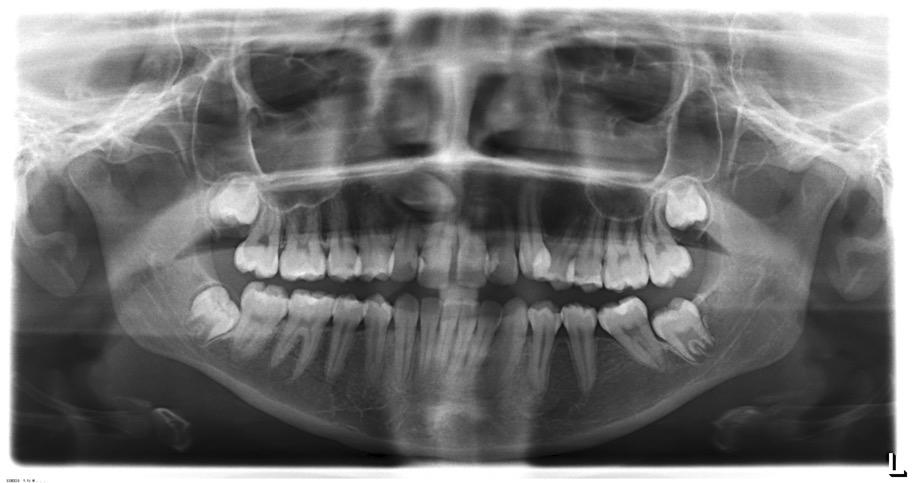

Ectopic canines are often one of the most challenging cases to treat as the aetiology is still unclear and the treatment is time sensitive. The practitioners –both GDPs and Orthodontist – should suspect a maxillary canine to be impacted if it is not palpable by 10-11 years of age and correlate it to other clinical findings and confirm diagnosis with radiographic examination by either a periapical radiograph or an Orthopantogram (OPG). Only 20% of the onethird children needing treatment get the interceptive treatment, which makes the impacted canine cases more difficult to treat resulting in losing the canine tooth as part of orthodontic extractions instead of a premolar in a crowding case or leaving the retained deciduous canine in situ and extracting the permanent canine due to unfavourable positioning. Not all canines are straight forward but with careful and timely diagnosis, the incidence of correction of impacted canines can definitely increase.

Audits were done in the region by the local Managed Clinical Network (MCN) and the average referral age for impacted canines was 14 years which is quite late and causes higher risk of root resorption of adjacent teeth, larger displacement of the tooth from its normal position, longer treatment time, greater morbidity and burnt compliance of the patient and greater load on the NHS.

The LDN – Local Dental Network NHS England Midlands has been taking the initiative to support the local GDPs by equipping them with knowledge to make better decisions. Courses have been organised in Shropshire and Staffordshire by the LDN chair for Staffordshire & Shropshire NHS England Midlands, Mr Tony Ahmed, who has been a great person to work with, and is very passionate towards advancing the delivery of high-quality orthodontic services across the region. The canine awareness course for practitioners

in Staffordshire was conducted in January 2025 at the Stafford postgraduate centre and another one is planned to take place in June in Shropshire. The course was attended by 20 delegates.

The goal was on completion of this course, the practitioners would have gained the skills to confidently diagnose and refer patients with impacted maxillary canines and to provide an overview of options for management of this common condition. Triaging patients appropriately plays a major role in the provision of orthodontics on the NHS, ensuring to diagnose and refer in a timely fashion either to primary care orthodontist or secondary care depending on complexity of the case.

The course was very well received and got excellent feedback. The delegates found the examples of clinical

cases most useful which stimulated the decision making along with academic knowledge.

1 -The UR3 on the OPG is not favourable for expose and bond and was therefore extracted.

2 – A late referral (patient aged 15) with 4 impacted permanent canines and untreated dental pathology